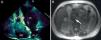

A)El ecocardiograma transtorácico en plano apical de 4 cámaras muestra un trombo de gran tamaño a nivel de la aurícula derecha que se desplaza hacia el ventrículo derecho en diástole. AD: aurícula derecha; AI; aurícula izquierda; Tr: trombo; VD: ventrículo derecho; VI: ventrículo izquierdo. B)La RM abdominal muestra trombosis a nivel de la vena cava inferior (flecha).

Consultó por disnea de mínimos esfuerzos de una semana de evolución. En la radiografía de tórax no se apreciaban hallazgos de interés. Destacaba un dímeroD de 1.141ng/ml por método de ELISA rápido, por lo que se realizó una gammagrafía pulmonar que confirmó la presencia de tromboembolismo pulmonar bilateral. El ecocardiograma transtorácico (fig. 1A) mostró una gran masa a nivel de la aurícula derecha que se desplazaba hacía el ventrículo en diástole, con extensión a la vena cava inferior (VCI). Se realizó una resonancia magnética (RM) toracoabdominal (fig. 1B) que confirmó la trombosis, que ocupaba la totalidad de la luz a nivel de las venas ilíacas comunes, la VCI y se extendía hasta la aurícula derecha. Se apreciaba realce tras la administración de gadolinio en la imagen del trombo de vena cava inferior, un dato que va a favor de trombosis tumoral.